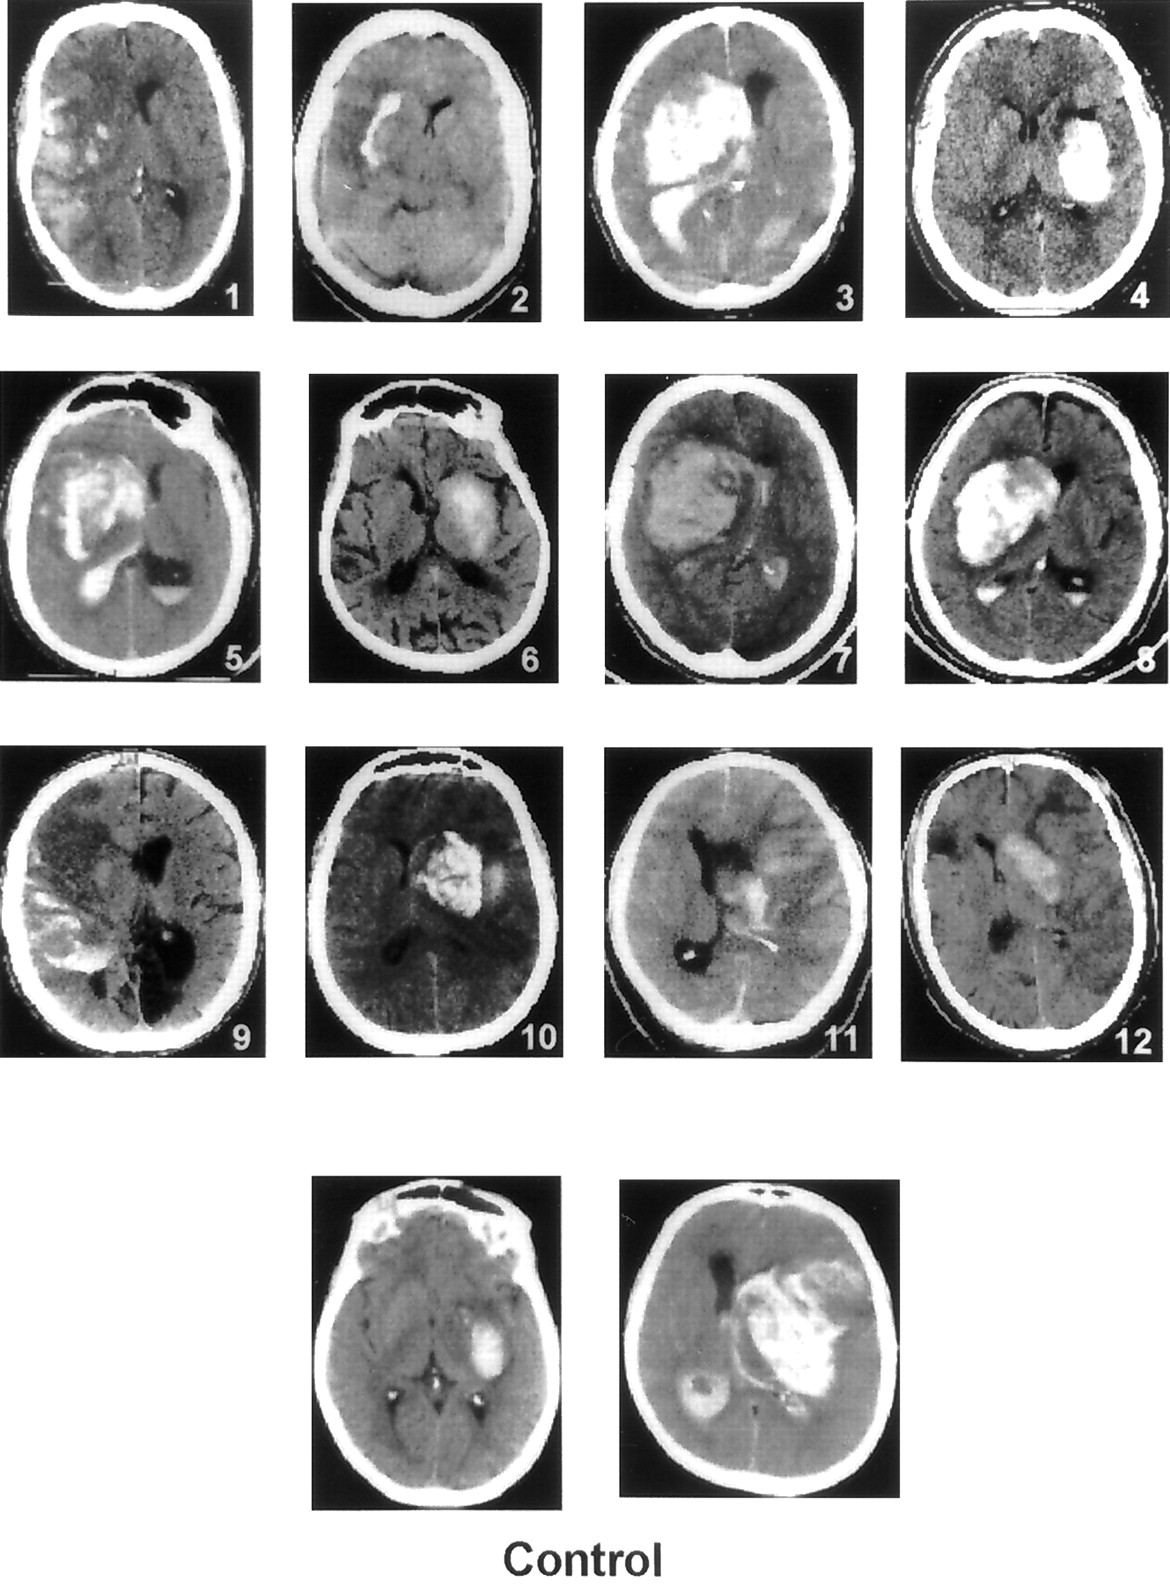

出血症状发生在110年的12个病人(10.9%)接受r-proUK和64年的两个(3.1%)接受静脉注射肝素。这种差异不显著(p= 0.086;相对危险度(RR) 3.5;95%可信区间,0.8 - 31.5)。这些14的CT扫描我的实例所示图2。r-proUK-treated病人的出血与两大支流出血性梗塞(例1、9和11)或大型深半球血肿(例3至8和10),而其他人则相对较小的出血性区域内大型hypodense水肿MCA梗塞分布(例2和12)。所有这些出血发生在前面的梗塞的面积,第一我的症状出现在平均10.2±7.4小时后开始治疗。治疗中风发作的间隔和时间与r-proUK 12出血症状的患者(5.17±0.9小时)不同,剩下的98名患者没有出现出血症状(5.14±0.8小时)。